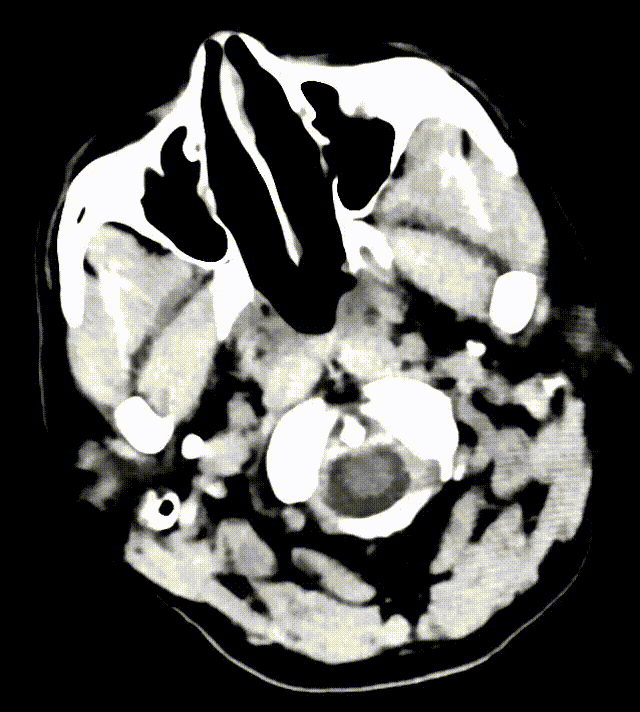

07 手术过程

主动脉弓造影:主动脉弓呈"Ⅰ"型弓,依次发出头臂干、左侧颈总动脉起及左侧锁骨下动脉,以上三支血管开口未见无明显狭窄、扩张及斑块形成,前向血流正常。

猪尾巴导管行全脑血管造影,可见双侧椎动脉V4段闭塞。

左侧椎动脉造影提示左侧椎动脉V4段闭塞;右侧锁骨下动脉造影提示右侧椎动脉纤细并V4段闭塞。

运用BASIS技术植入3.0*25mm Syphonet®取栓支架,输送球囊对闭塞段进行扩张。

运用BASIS技术回收3.0*25mm Syphonet®取栓支架及5F 125cm Tethys®中间导引导管,取出血栓;

复查造影:左侧椎动脉、双侧大脑后动脉、小脑上动脉、小脑前下动脉显影正常。